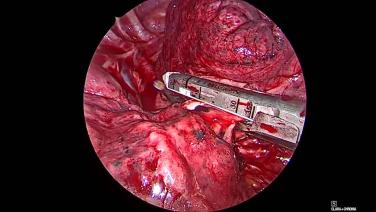

Thorascopic Lobectomy - Staple and Divide the Lobar Bronchus